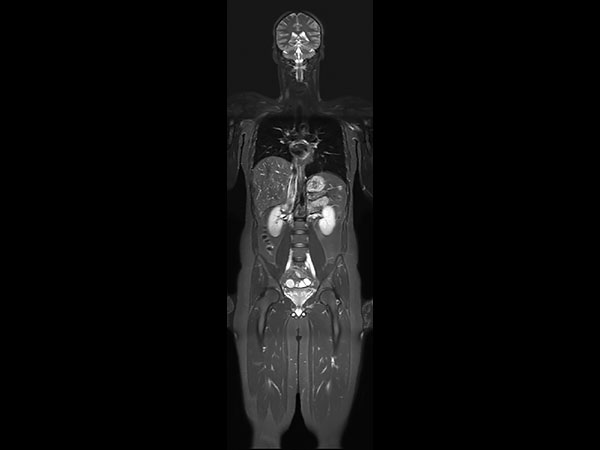

A 33-year-old male with history of non-Hodgkin lymphoma undergoes an MRI exam on Ingenia 1.5T to visualize clinically suspected recurrent disease. Whole-Body MRI was performed using T1W TSE and STIR imaging (4 stations, matrix 400x400, 6 mm slices). Additional whole-body diffusion imaging (3 stations, matrix 192x192, 6 mm slices) with MIP unmasks a focal area of diffusion restriction in the left scapular region. Subsequent contrast-enhanced 3D mDIXON imaging reveals a bone manifestation of a lesion in the left scapular angle. Furthermore, multifocal splenic infiltration is depicted. Note that the splenic lesions are veiled by the high physiological background diffusion signal in splenic tissue. The findings are compatible with skeletal and splenic tumor recurrence of non-Hodgkin lymphoma. Further total body follow-up imaging according to therapeutic regime is advised. Whole-body MRI allows rapid visualization of lesions in this lymphoma patient. A finding of multifocal organ manifestations has a decisive impact on further patient management and therapeutic regime. The fully digital Ingenia 1.5T MR system allows for rapid whole-body MRI with homogenously high imaging quality in depicting these lesions. Additionally, state-of-the art techniques such as whole body DWI can be included in the exam protocol, which further enhances the capability for visualizing lesions in oncology patients.

Coronal T1w TSE

Coronal STIR